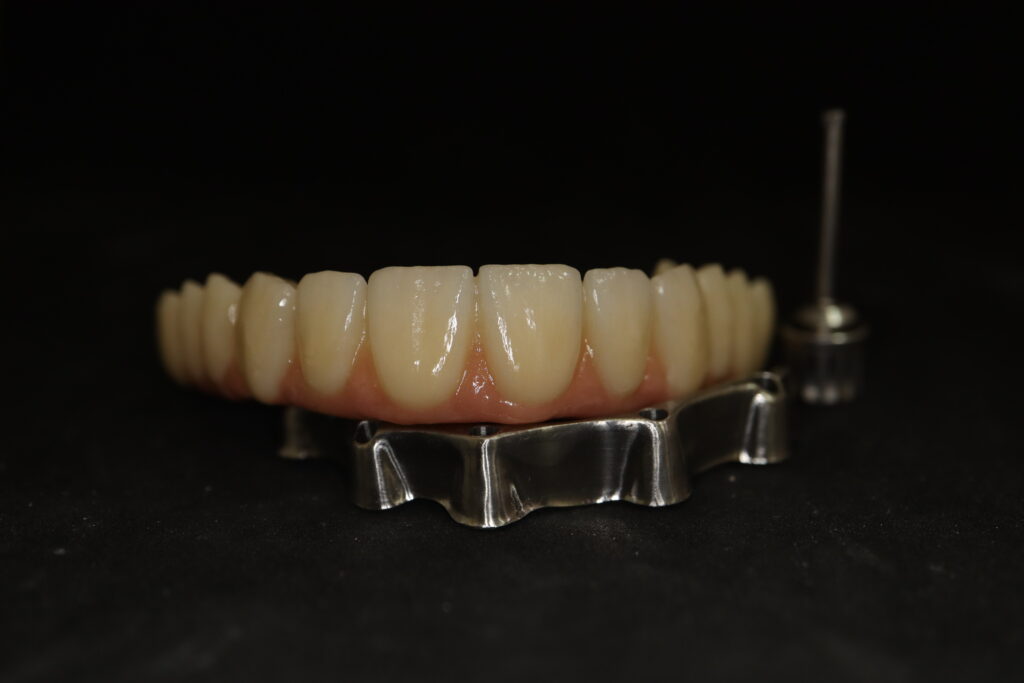

На консультации было принято решение о перепротезировании протезом из диоксида циркония на титановой балке.

Спустя 27 дней был зафиксирован протез с опопрой на дентальные имплантаты из диоксида циркония с каркасом из титана.

Также на нижнюю челюсть был изготовлен мостовидный протез из 4х коронок (цирконий) с опорой на 3 индивидуальных абатмента с одной стороны и 1 коронка на иплантат с другой.